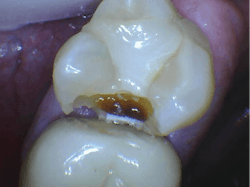

- Aren’t capable of showing initial or even deep dental caries (figures 1 and 2)

Lack of ability for current digital sensors to show initial dental caries. Clinicians have to wait too long before restoring teeth, which weakens the teeth, requires more time for the procedure, uses more material, and results in more difficult restorative procedures. Apparently, this problem cannot be overcome with the current generation of digital radiographs. Use of caries-detecting devices and careful magnified visual observation are the only current solutions.